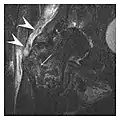

a

b

Figure 7: Fatigue fracture of the talus in a 25-year-old male basketball player with right hind foot and ankle pain, without history of trauma, and a normal initial radiograph (not shown). (a) One-month followup lateral radiograph shows normal appearance. (b) Sagittal T1-weighted MRI shows an irregular fracture line (arrow) within an ill-defined area of hypointensity corresponding to bone marrow edema.[1]

Fatigue fractures are more frequent in women which may be due to the relatively smaller bones of women. Moreover, pregnancy is a well-recognized risk factor for femoral neck fatigue fracture. While fibular and metatarsal fractures have a low risk of complications, other sites including the femoral neck, midanterior tibia, navicular, talar, and other intraarticular fractures are prone to complications such as delayed union, nonunion, and displacement. The site of the insufficiency fracture may be specific to the activity: for example, rugby and basketball players are more prone to navicular fractures, while gymnasts have a higher risk for talar fractures (Figure 7). Long distance runners are at increased risk for pelvic, tibial (Figures 8 and 9), and fibular fractures. In the military, calcaneus (Figure 10) and metatarsals are the most commonly cited injuries, especially in new recruits. Billiard players are at risk for upper limb fractures (Figure 11).[1]